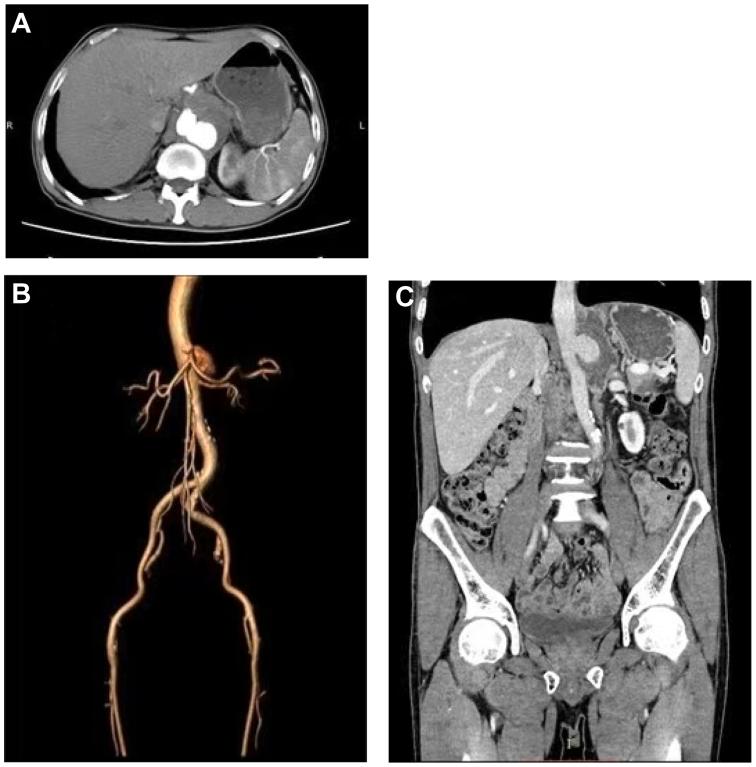

Tuberculous abdominal aortic pseudoaneurysm is a severe vascular disease that is exceptionally rare and carries a high risk of rupture. This article reports the rupture of a pseudoaneurysm in a 60-year-old male patient during anti-tuberculosis treatment. The patient's general condition was poor, making him unable to tolerate open surgical treatment. Therefore, endovascular aortic aneurysm repair was performed. The rupture site of the patient's aneurysm was located next to the visceral artery (between the superior mesenteric and renal arteries). During the surgery, we used three-dimensional printing technology to perform fenestrated endovascular repair. The surgery successfully excluded the aneurysm while ensuring blood supply to the visceral arteries. After discharge, the patient received regular anti-tuberculosis treatment. Postoperative follow-up revealed no graft-related complications, and the visceral artery remained unobstructed.

摘要

结核性腹主动脉假性动脉瘤是一种极为罕见的严重血管疾病,破裂风险很高。本文报道了一名60岁男性患者在抗结核治疗期间假性动脉瘤破裂的病例。患者一般状况较差,无法耐受开放手术治疗。因此,实施了血管腔内主动脉瘤修复术。患者动脉瘤的破裂部位位于内脏动脉旁(肠系膜上动脉和肾动脉之间)。手术中,我们使用三维打印技术进行开窗血管腔内修复。手术成功排除了动脉瘤,同时确保了内脏动脉的血供。出院后,患者接受了规律的抗结核治疗。术后随访未发现与移植物相关的并发症,内脏动脉保持通畅。